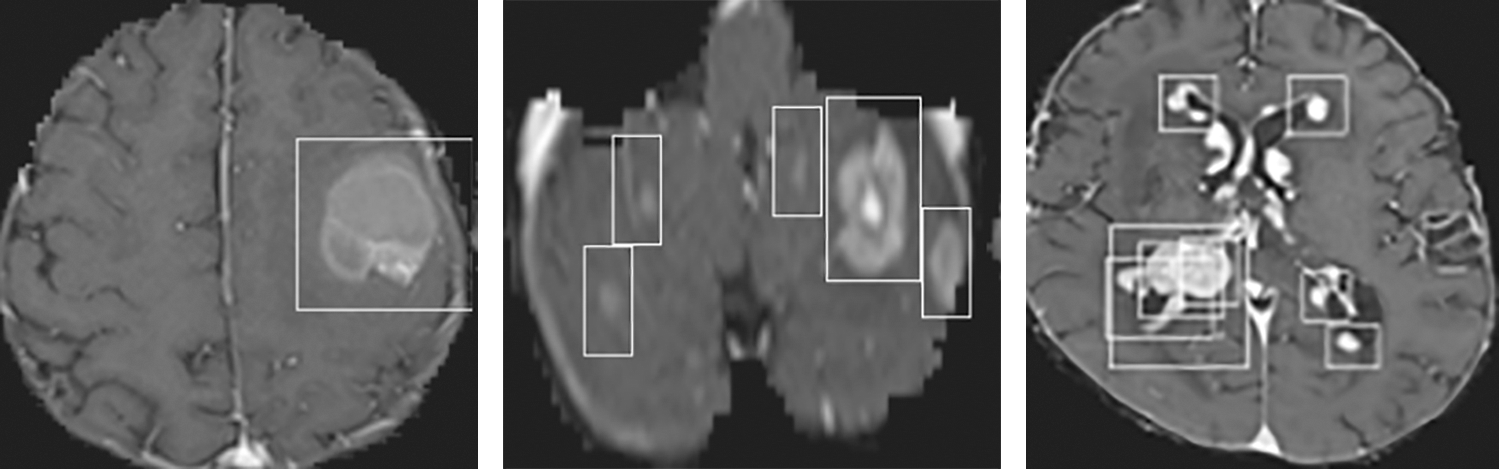

The accuracy and loss of the YOLOv3 model based on the training and testing dataset are also compared, and the results are shown in Fig. 15. Fig. 15a shows that the accuracy of the YOLOv3 model is increased from 0.729 to 0.819 and 0.478 to 0.943 using the training and testing dataset, respectively. However, the loss of the YOLOv3 model is decreased from 0.755 to 0.204 and 3.488 to 0.627 using training and testing datasets, respectively, as shown in Fig. 15b. Furthermore, the results of tumor localization in images using the YOLOv3 model are shown in Fig. 16.

Figure 16: Tumor Localization in images using the YOLOv3 model